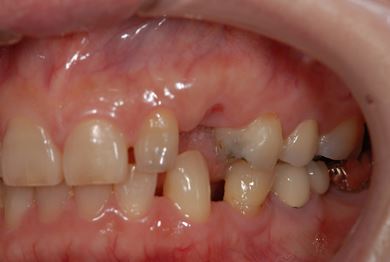

インプラントの症例写真 IMPLANT

インプラント治療

| 主訴 | 乳歯がぐらついている。 | ||||||||||||||||||||||||||||||||

| 治療方針 | インプラント治療にて、機能的・審美的回復を行う。 | ||||||||||||||||||||||||||||||||

| 治療内容 | インプラント1本、メタルボンドセラミッククラウン1本 | ||||||||||||||||||||||||||||||||